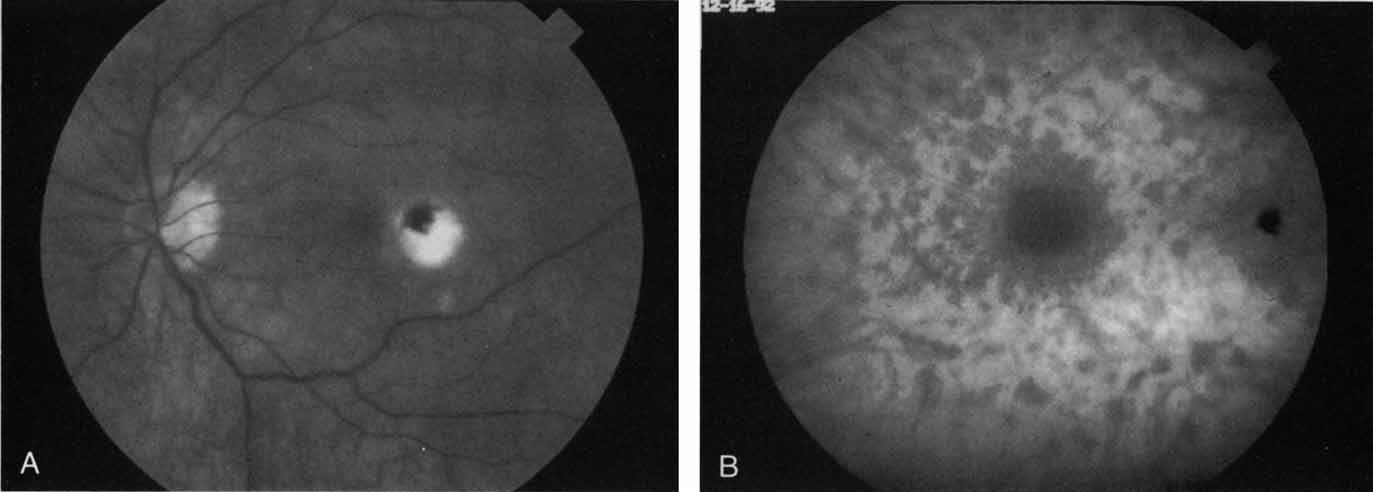

In acute multifocal posterior placoid pigment epitheliopathy, discrete hypofluorescent geographic areas are present both in the posterior pole and extending into the mid-periphery on ICG angiography65,66 (Fig. 16). These hypofluorescent areas are more extensive than noted on either clinical or fluorescein angiographic examination. They are noted in the early phases of the ICG study and persist late, suggesting that ischemic changes in the choroidal circulation occur in this disease. The hypofluorescence remains even once lesions have healed.

Fig. 16 A. Clinical photograph of a patient with acute multifocal placoid pigment epitheliopathy (AMPPE). There is extensive involvement of the central macula by the inflammatory lesions. B. Late-phase indocyanine green angiogram demonstrating extensive confluent but irregular areas of marked hypofluorescence. The hypofluorescence in AMPPE is believed to represent a perfusion abnormality within the choroidal circulation.